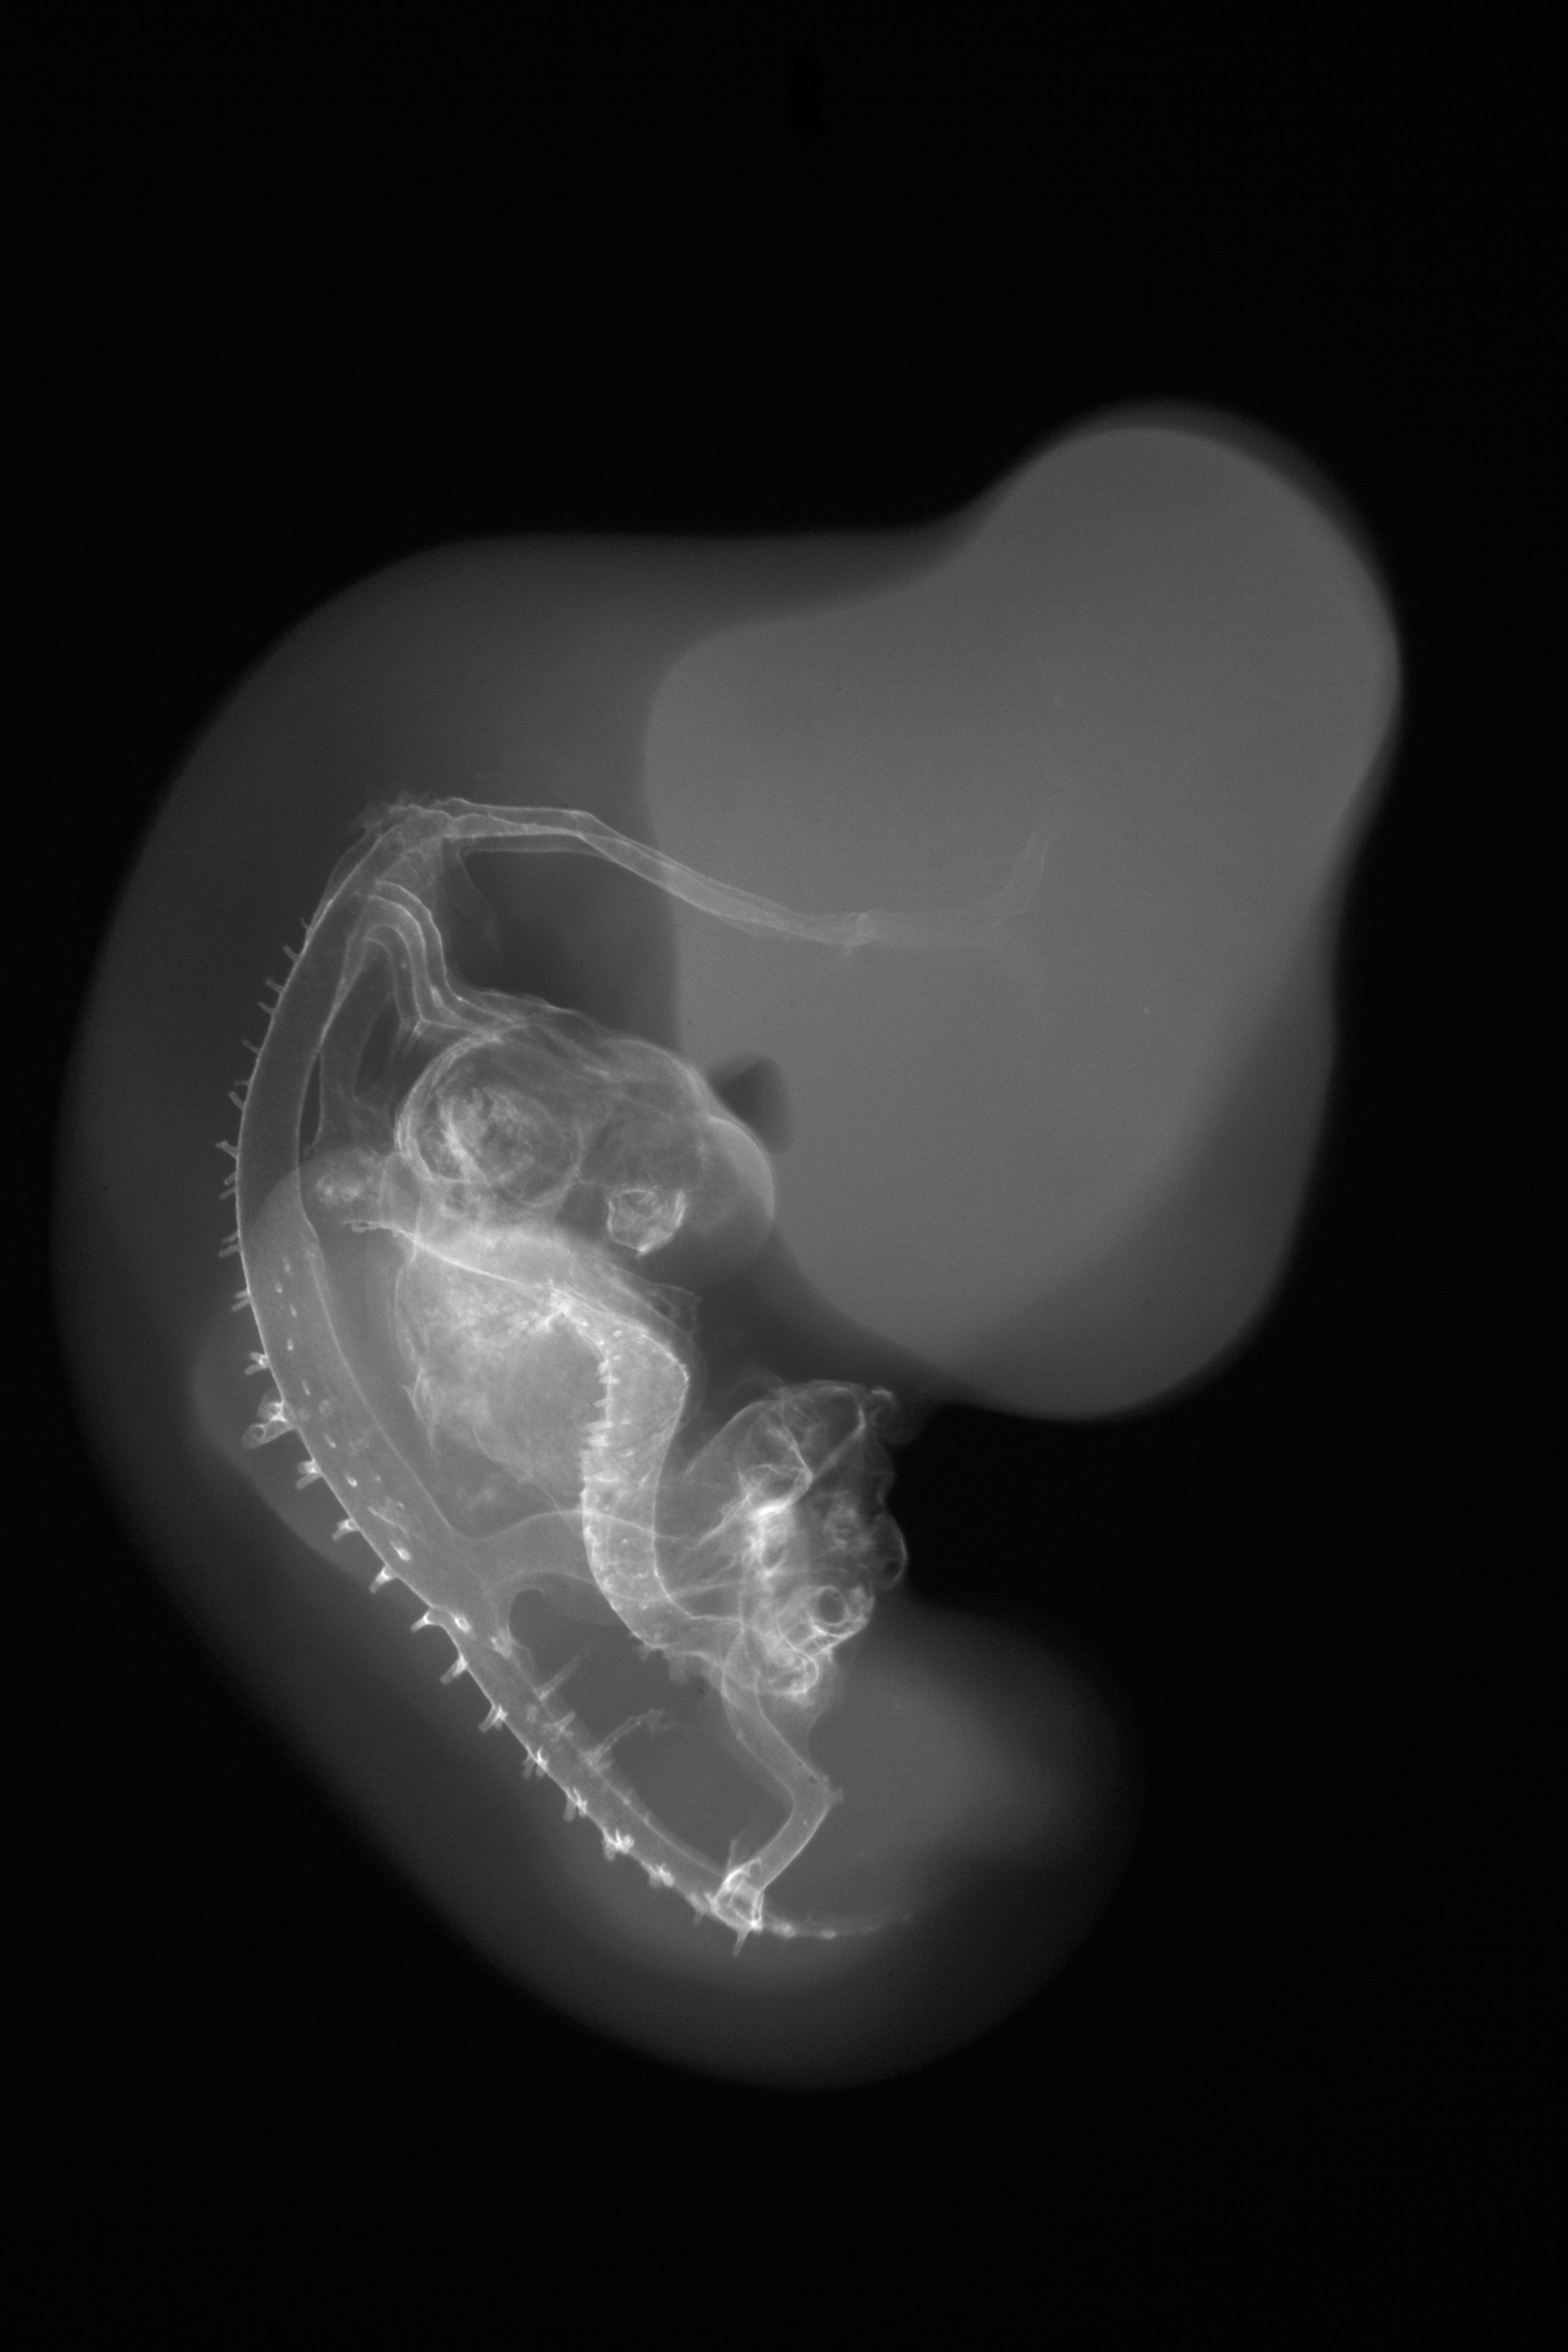

Chick Embryo Microangiography

Hamburger-Hamilton (HH) Stage 27 (approx. 5 - 5.5 days)

X-Ray Micrographs